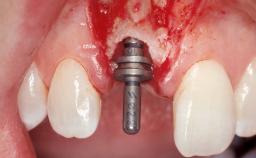

Late Flapless Placement of an Implant in a Maxillary Left Central Incisor Site

A 39-year-old male patient presented with a chief complaint of discomfort and gingival discoloration around his maxillary left central incisor. He was in good general health and was a non-smoker. His past dental history was significant because of the traumatic fracture of tooth 21 in a sporting accident at age 13. Initial dental treatment included endodontic therapy and a full-coverage restoration. The patient became symptomatic 5 years later, when structural failure of the tooth resulted in the dislodgment of the crown. Endodontic retreatment, apical surgery, and post-and-core restoration were performed.

Bone Augmentation Horizontal|Staged

Augmentation Materials Xenogenous|Membrane